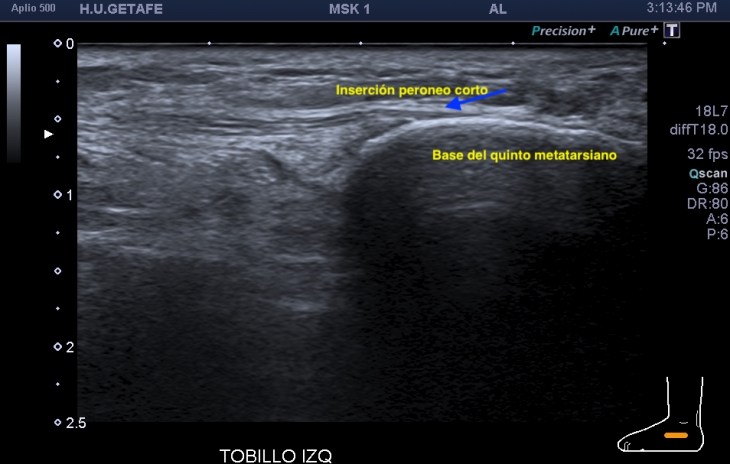

Evidentemente es una imagen patológica comparada con una normal contralateral, la anatomía de la región patológica está cambiada, el hueso está irregular, comparativamente con la zona normal. Esos cambios en el hueso se visualizan en la espina iliaca inferior, donde inserta el tendón del recto anterior, pero este tendón no solo inserta fibras ahí, sino que algunas de ellas insertan justo en la región superior del acetábulo,imagen 3, es decir, justo antes de la inserción en la espina iliaca anteroinferior, algunas se bifurcan hacia profundo, buscando el acetábulo.

La imagen 2 es centrándonos en la zona de patología, aún más espectacular. Se observa la deformación global del hueso en esa zona marcado con flecha amarilla plana.

Explorar esta zona de inserción es complejo, el recto anterior, que luego es el tendón intramuscular o rafe del recto anterior del cuadriceps, inserta mediante su tendón buscando la profundidad en la cadera, con lo que encontramos anisotropía…te voy a enseñar una forma de explorarlo donde vas a poder corregir esa anisotropía. La exploración habitual es con la pierna en extensión y decúbito supino, pero vamos a pedir al paciente que se siente en la camilla, baje la pierna y apoye el talón del pie, el tronco del paciente mínimamente inclinado hacia atrás, la cadera y la rodilla en extensión y la sonda colocada en la zona de inserción…la imagen que logras es esta maravilla, imagen 3.

Cuando en la zona de inserción en la EIA inferior tiene cambios en la inserción del tendón se verán imágenes de calcificación lineal de la inserción, cuando esos cambios son muy llamativos tenemos la imagen 1 y 2, cuando son menos llamativos la imagen 4, pero ojo que ambos pueden dar clínica a valorar por los médicos especialistas.

Es importante que conozcas la zona, la anatomía, y que pruebes la proyección que te he explicado, verás esas fibras insercionales muy bien porque corriges la anisotropía.